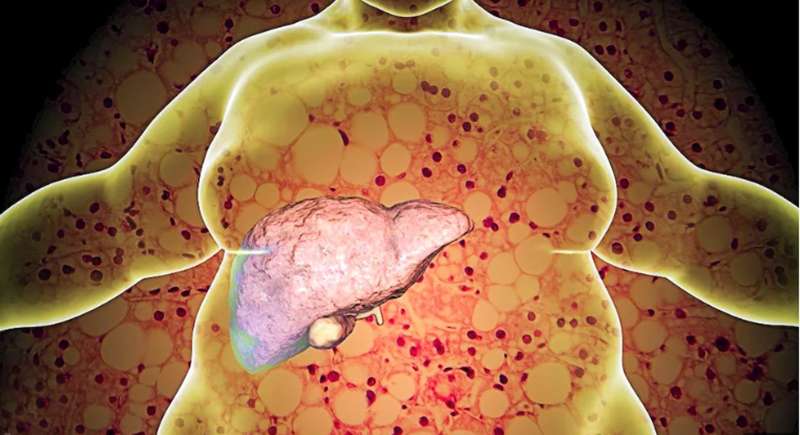

क्या है फैटी लिवर? जानिए इसकी मूल पहचान

आजकल फैटी लिवर एक बड़ी समस्या बनता जा रहा है, लेकिन इसके लिए केवल मोटापा नहीं नहीं, बल्कि डायबिटीज, शराब, हार्मोनल असंतुलन समेत कई बातें जिम्मेदार हो सकती हैं. अगर समय पर जांच हो जाए, तो इस समस्या को ठीक किया जा सकता है. आइए एक्सपर्ट से जानते हैं कि फैटी लिवर के क्या कारण हो सकते हैं. बदलती लाइफस्टाइल की वजह से फैटी लिवर लोगों के लिए एक बड़ी मुश्किल बन रहा है. ये बीमारी जहां पहले बड़े-बुजुर्गों में देखी जाती थी, तो वहीं अब ये बीमारी युवाओं और बच्चों को भी शिकार बना रही है. फैटी लिवर के शुरुआत में कोई खास लक्षण नहीं दिखते, लेकिन अगर समय रहते इलाज न मिले, तो सिरोसिस, लिवर फेलियर या लिवर कैंसर का खतरा बढ़ जाता है. अक्सर लोग ये मान लेते हैं कि सिर्फ मोटापा ही फैटी लिवर की मुख्य वजह है, लेकिन वास्तव में और भी कई ऐसी बातें हैं, तो फैटी लिवर के लिए जिम्मेदार हो सकती हैं. आइए एक्सपर्ट से जानते हैं सबसे पहले कि फैटी लिवर क्या होता है और यह कैसे होता है. साथ ही इसके कारण क्या होते हैं.

फैटी लिवर क्या है?

लेडी हर्डिंगें हॉस्पिटल में मेडिसिन विभाग में प्रोफेसर एलएस घोटकर बताते हैं कि जब लिवर की कोशिकाओं में सामान्य से अधिक फैट जमा हो जाता है. तो ये फैट लिवर के सामान्य कामकाज में मुश्किल पैदा करने लगता है. साथ ही कुछ समय बाद लिवर को नुकसान पहुंचा सकता है. ऐसी स्थिति को फैटी लिवर कहते हैं. इसमें मरीज के पेट में दर्द, भूख की कमी, शरीर में थकान और कमजोरी जैसे कई लक्षण दिखने लगते हैं. अगर किसी भी मरीज को पेट के दाहिने हिस्से में दर्द हो या भूख की कमी हो तो उसे सतर्क हो जाना चाहिए.